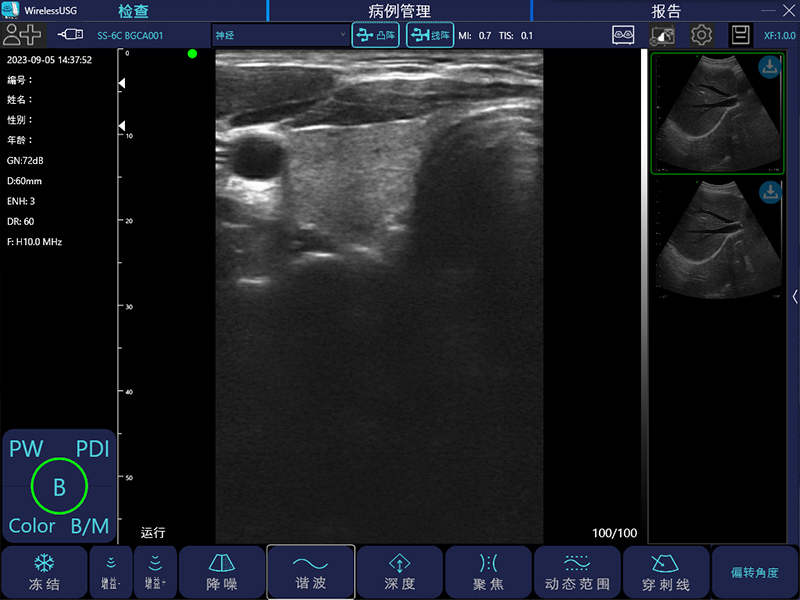

- 成像模式: B、B/M、Color、PW、PDI

- 探头类型:凸阵、线阵、相控阵、微凸、腔内、直肠

线阵:7.5MHz/10MHz,20/40/60/100mm,40mm

- 图像调节:黑白图像增益、分段增益TGC、动态范围、焦点、深度、反相脉冲谐波、降噪、彩色增益、血流采样框大小、PRF

- 穿刺辅助功能:平面内穿刺引导线功能,平面外穿刺引导与血管自动计测功能